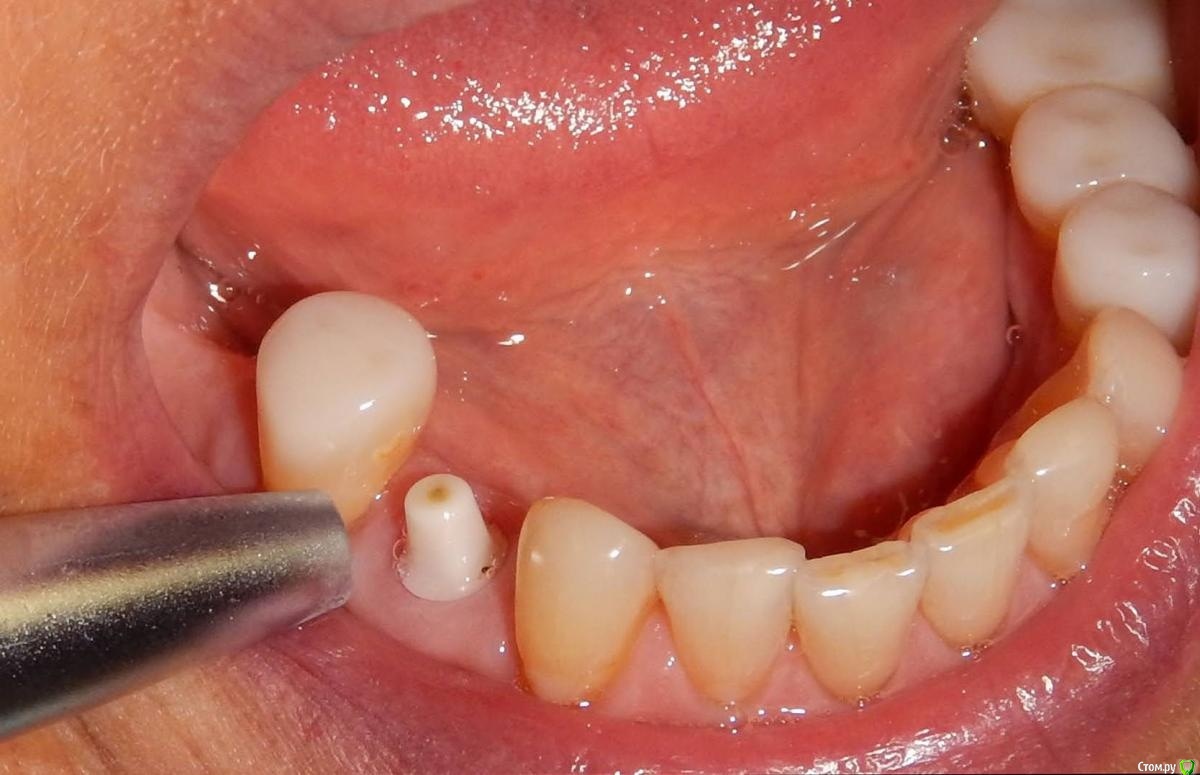

Astronaft Опубликовано 25 января, 2021 Автор Поделиться Опубликовано 25 января, 2021 Спасибо.День операции, 12 недель, день цементировки. 3 1 Ссылка на комментарий

Astronaft Опубликовано 25 января, 2021 Автор Поделиться Опубликовано 25 января, 2021 Уступ доводили вручную? Чем?Имплантат не трогал. На фото черная застёжка (snap on) для оттиска закрытой ложкой - это фабричная деталь. Если доведётся когда-либо доводить уступ - красный алмазный бор. Мелкая алмазная пыль даёт меньшее количество микротрещин. Ссылка на комментарий

Astronaft Опубликовано 24 января, 2021 Поделиться Опубликовано 24 января, 2021 (изменено) Одиночный цирнокиевый имплантат и расщепление без графта. Пациентка:тонкая хрупкая женщина 55 лет, сконцентрированная на своем здоровье, в некоторой мере мнительная.всегда тяжелые заживления после удалений (по опросам)есть результаты Клиффорд теста (такая книжка под 200 страниц с in vitro аллерго-пробами на все известные материалы) Поставленная цель:только цирконий Мне было интересно найти вариант найболее приемленый пациентке и мне. С минимом хирургического риска и риском сожаления пациентки про выбор костного материала. Во-первых, я не использую аллографты - философски, чужие протеины, неприятный запах - просто основываясь на своем мнении.Во-вторых, мнительные пациенты склонны "пойти и почитать" до или потом и как следствие внушить себе вещи которых может и не было. Но по скольку мысль материальна... Все обсудил заранее.План: ридж сплит (расщепление), имплантат без графта, свободный СТ графт; если случается вестибулярная рецессия - пилим зирконий во рту. Ридж сплит сделан пьезотомом - крестальный и вертикальные пропилы на глубины около 8-10мм.Пилотное сверло.Развдвинул кость остеотомами от 1.6мм до 3.5мм в диаметре.Очень мягкая кость - напомнила мегкую максиллу плотности ногтевой пластинки вестибулярно.Имплант встал легко, но торк 40нсм. СТ графт из области 18. Деэпителизирую скальпелем уже потом. Тут интересно отметить, что я перестал боятся ошметков эпителия.Пончо сверху имплантата (а-ля шашлык Карлоса).Швы. PTFE всегда хорош. 12 недель.Красивая десна.Периотест -5.8 - отличный результат.Оттиск. Циркониевая коронка симметричная другой стороне. Изменено 24 января, 2021 пользователем Astronaft 19 Ссылка на комментарий